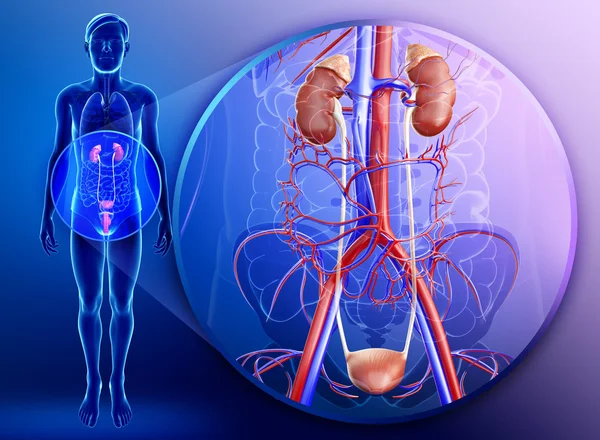

Vizeletelvezető rendszer

Ezen a képen a vesék hasüregben való elhelyezkedését, valamint a vizeletelvezető rendszert láthatjuk. A bordaív alatt a hasüreg hátsó részében helyezkednek el a vesék. Ezektől vezet a húgyvezeték egészen a kismedencében elhelyezkedő húgyhólyagig.

2. kép:

Vese

Egy sematikus ábrát láthatunk a veséről. A vese parenchyma 2 részből áll, a velő (medulla) és a kéreg (cortex) állományból. A vizelet a vesemedencében gyűlik össze (pelvis), ahonnan a húgyvezetéken (ureter) keresztül távozik a hólyag irányába. Láthatjuk, hogy a vesemedencében relatív nagyobb tér áll rendelkezésre mint a hugycsőben, ami miatt a fent keletkezett nagyobb kövek nagyobb eséllyel akadhatnak el a szűkebb húgycsőben. A vesének azt a részét ahol a vizeletelvezető rendszer kilép a veséből kapunak nevezik. A vesét ellátó erek is itt lépnek be illetve ki a veséből.